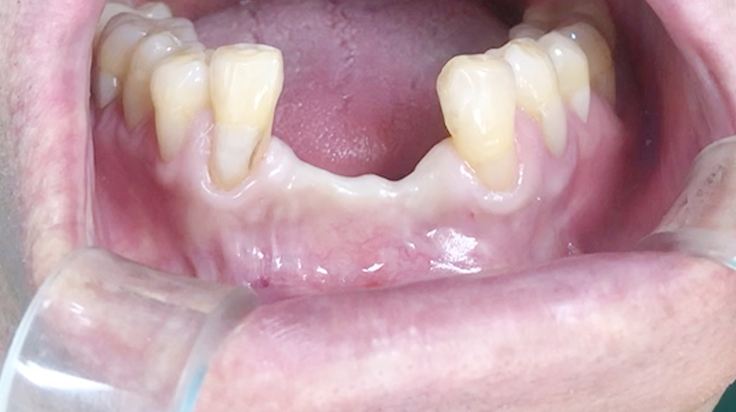

Horizontal ridge augmentation

A surgical procedure to increase the width of alveolar ridge which have been resorbed after tooth or teeth were lost